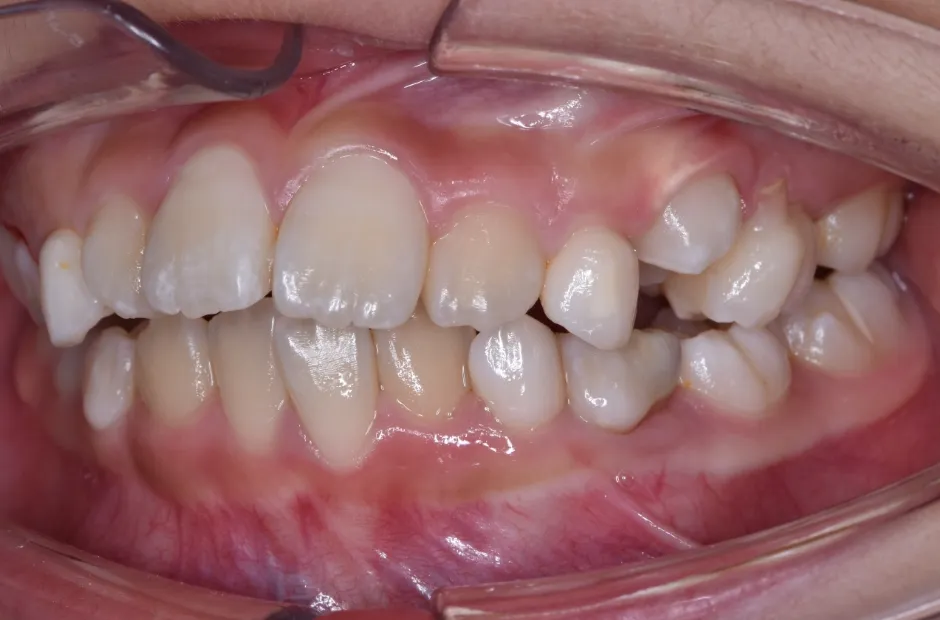

治療症例

ブラケット矯正

前歯部反対咬合

| 診断名・主訴 | 前歯部反対咬合 |

|---|---|

| 年齢・性別 | 14歳・男性 |

| 治療期間・回数 | 1年2か月 |

| 治療に用いた主な装置 | ブラケット矯正 |

| 抜歯部位 | なし |

| 治療費 | 60万円(税抜) |

| リスク・副作用 | 装置による違和感・疼痛・歯肉退縮・歯根吸収・虫歯のリスクなど |

治療前

治療中

治療後